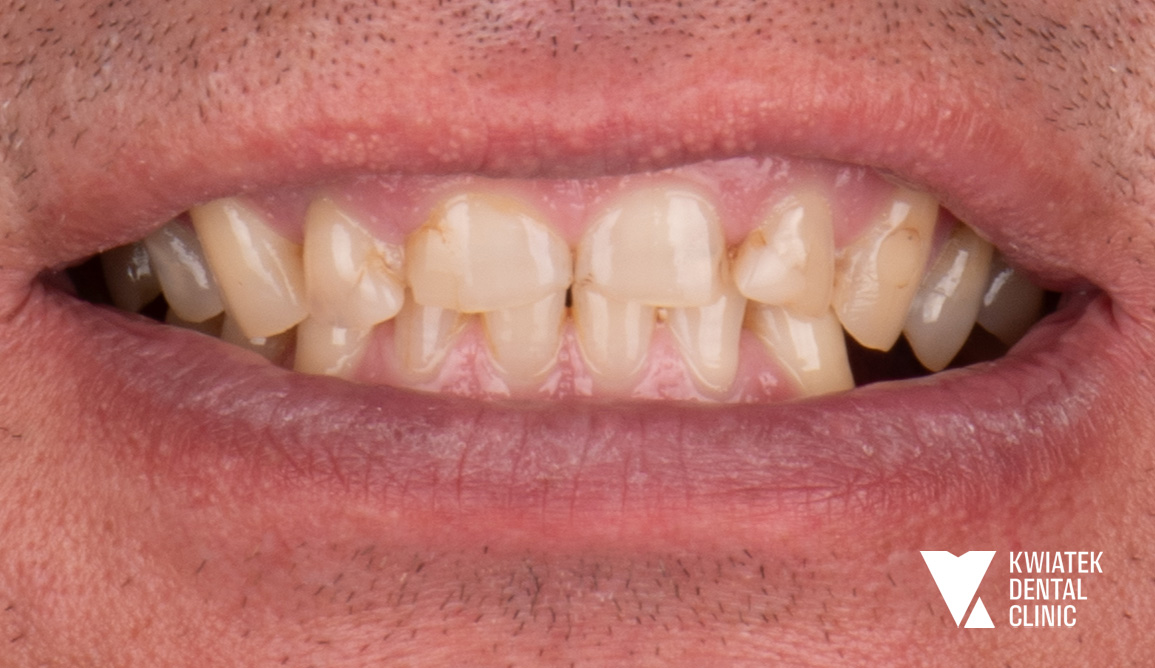

Pełna rekonstrukcja zwarcia i estetyki - historia wymagającej metamorfozy

Pacjent zgłosił się do kliniki z zaawansowanymi problemami stomatologicznymi: licznymi ubytkami próchnicowymi, brakami zębowymi, starciem zębów oraz zaburzeniami zwarcia. Leczenie obejmowało kompleksową diagnostykę, leczenie zachowawcze i endodontyczne, zabiegi chirurgiczne, implantację oraz wieloetapową odbudowę protetyczną. Efektem terapii jest perfekcyjnie zbalansowany zgryz, najwyższy komfort funkcjonowania oraz naturalnie piękny uśmiech, który podkreśla indywidualny charakter pacjenta i pozwala mu w pełni cieszyć się nim każdego dnia.